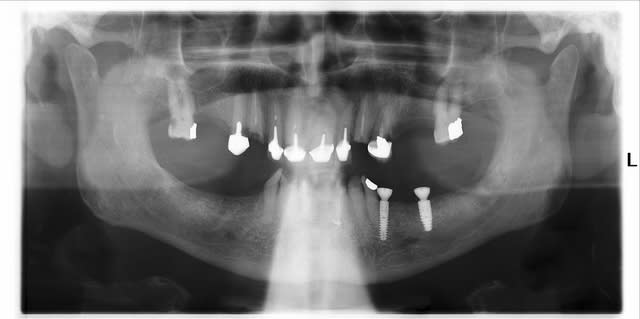

Il y a quelques mois, j'envoie un jeune patient de 80ans pour avulsion de la 38 cassée qui le gêne.

Je découvre 2 corps étrangers secteur 3.

- le stomato lui a conseillé d'en mettre pour mieux manger et va le revoir pour lui poser un bridge.

- le reste il lui dit que ce n'est pas grave, mais que sinon il peut me revoir...

- dans le secteur, il n'y pas d'antagonistes puisque rien ne va être remis et que les dents sont délabrées.

Après le All-On-Four, voici le Nothing-On-Two

Et en plus il lui a flingué la 34

t'exagères, il y a quand même 2 vis de cicatrisation :)